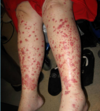

A: Name the 2nd most common Skin Tumor

B: Risk Factors (11)

C: What’s the BIGGEST Risk Factor and why

A: Squamous Cell Carcinoma

B: HAIR IN WOMBS

- [HRAS activating mutation]

- Arsenic

- Immunosuppresion (HPV)

- Radiation-ionizing

- Industrial

- [Notch receptor LOSS OF FUNCTION mutation]

- Wounds-chronic

- Older

- Males

- Burn Scars

- SUN!!!!! = BIGGEST RISK FACTOR!

C: Sun–>[TP53 mutation at pyrimidine dimers] (INC potential in Xeroderma Pigmentosum pts)